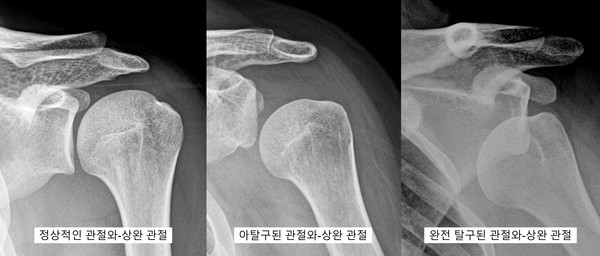

김두한 교수_ 위 그림처럼 어깨에는 2개의 관절이 있습니다. 쇄골과 날개뼈의 견봉과 만나서 이루는 1. 견봉-쇄골관절, 상완골과 날개뼈의 관절와 부분이 만나는 2. 관절와-상완 (glenohumeral) 관절이 있습니다.

이 두 관절을 모두 탈구가 일어날 수 있으며, 그 중에서도 흔하게 접할 수 있고 높은 빈도로 탈구가 발생하는 관절은 관절와-상완관절 탈구 (glenohumeral dislocation)입니다. 전방으로 빠지는, 즉 상완골이 관절와 앞으로 탈구되는 것이 가장 흔합니다.

김두한 교수_ 탈구에도 완전탈구(complete dislocation)가 있고 아탈구(subluxation)가 있습니다. 완전탈구는 말 그대로 완전히 관절면을 벗어나 관절의 조화로운 상태가 파괴되는 탈구입니다. 아탈구는 완전한 탈구가 없이 관절면이 살짝 어긋난 경우로 정의합니다. 커리의 경우 관절와-상완 관절이 아탈구가 일어났다가 다시 관절면이 유지된 상태로 생각되며, 관절막이나 인대가 조금 늘어난, 즉 인대손상 1단계 정도가 진단이 되었을 것으로 생각됩니다. 그렇기 때문에 1달 전후로 무사히 복귀를 할 수 있었던 것 같습니다.